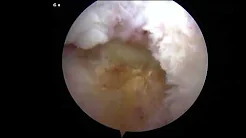

Arthroscopic Rotator Cuff Repair with Dermal Collagen Allograft Patch